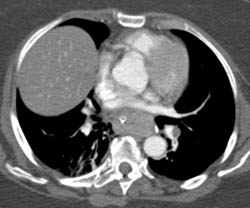

Crohn's With Prominent Vasa Recta